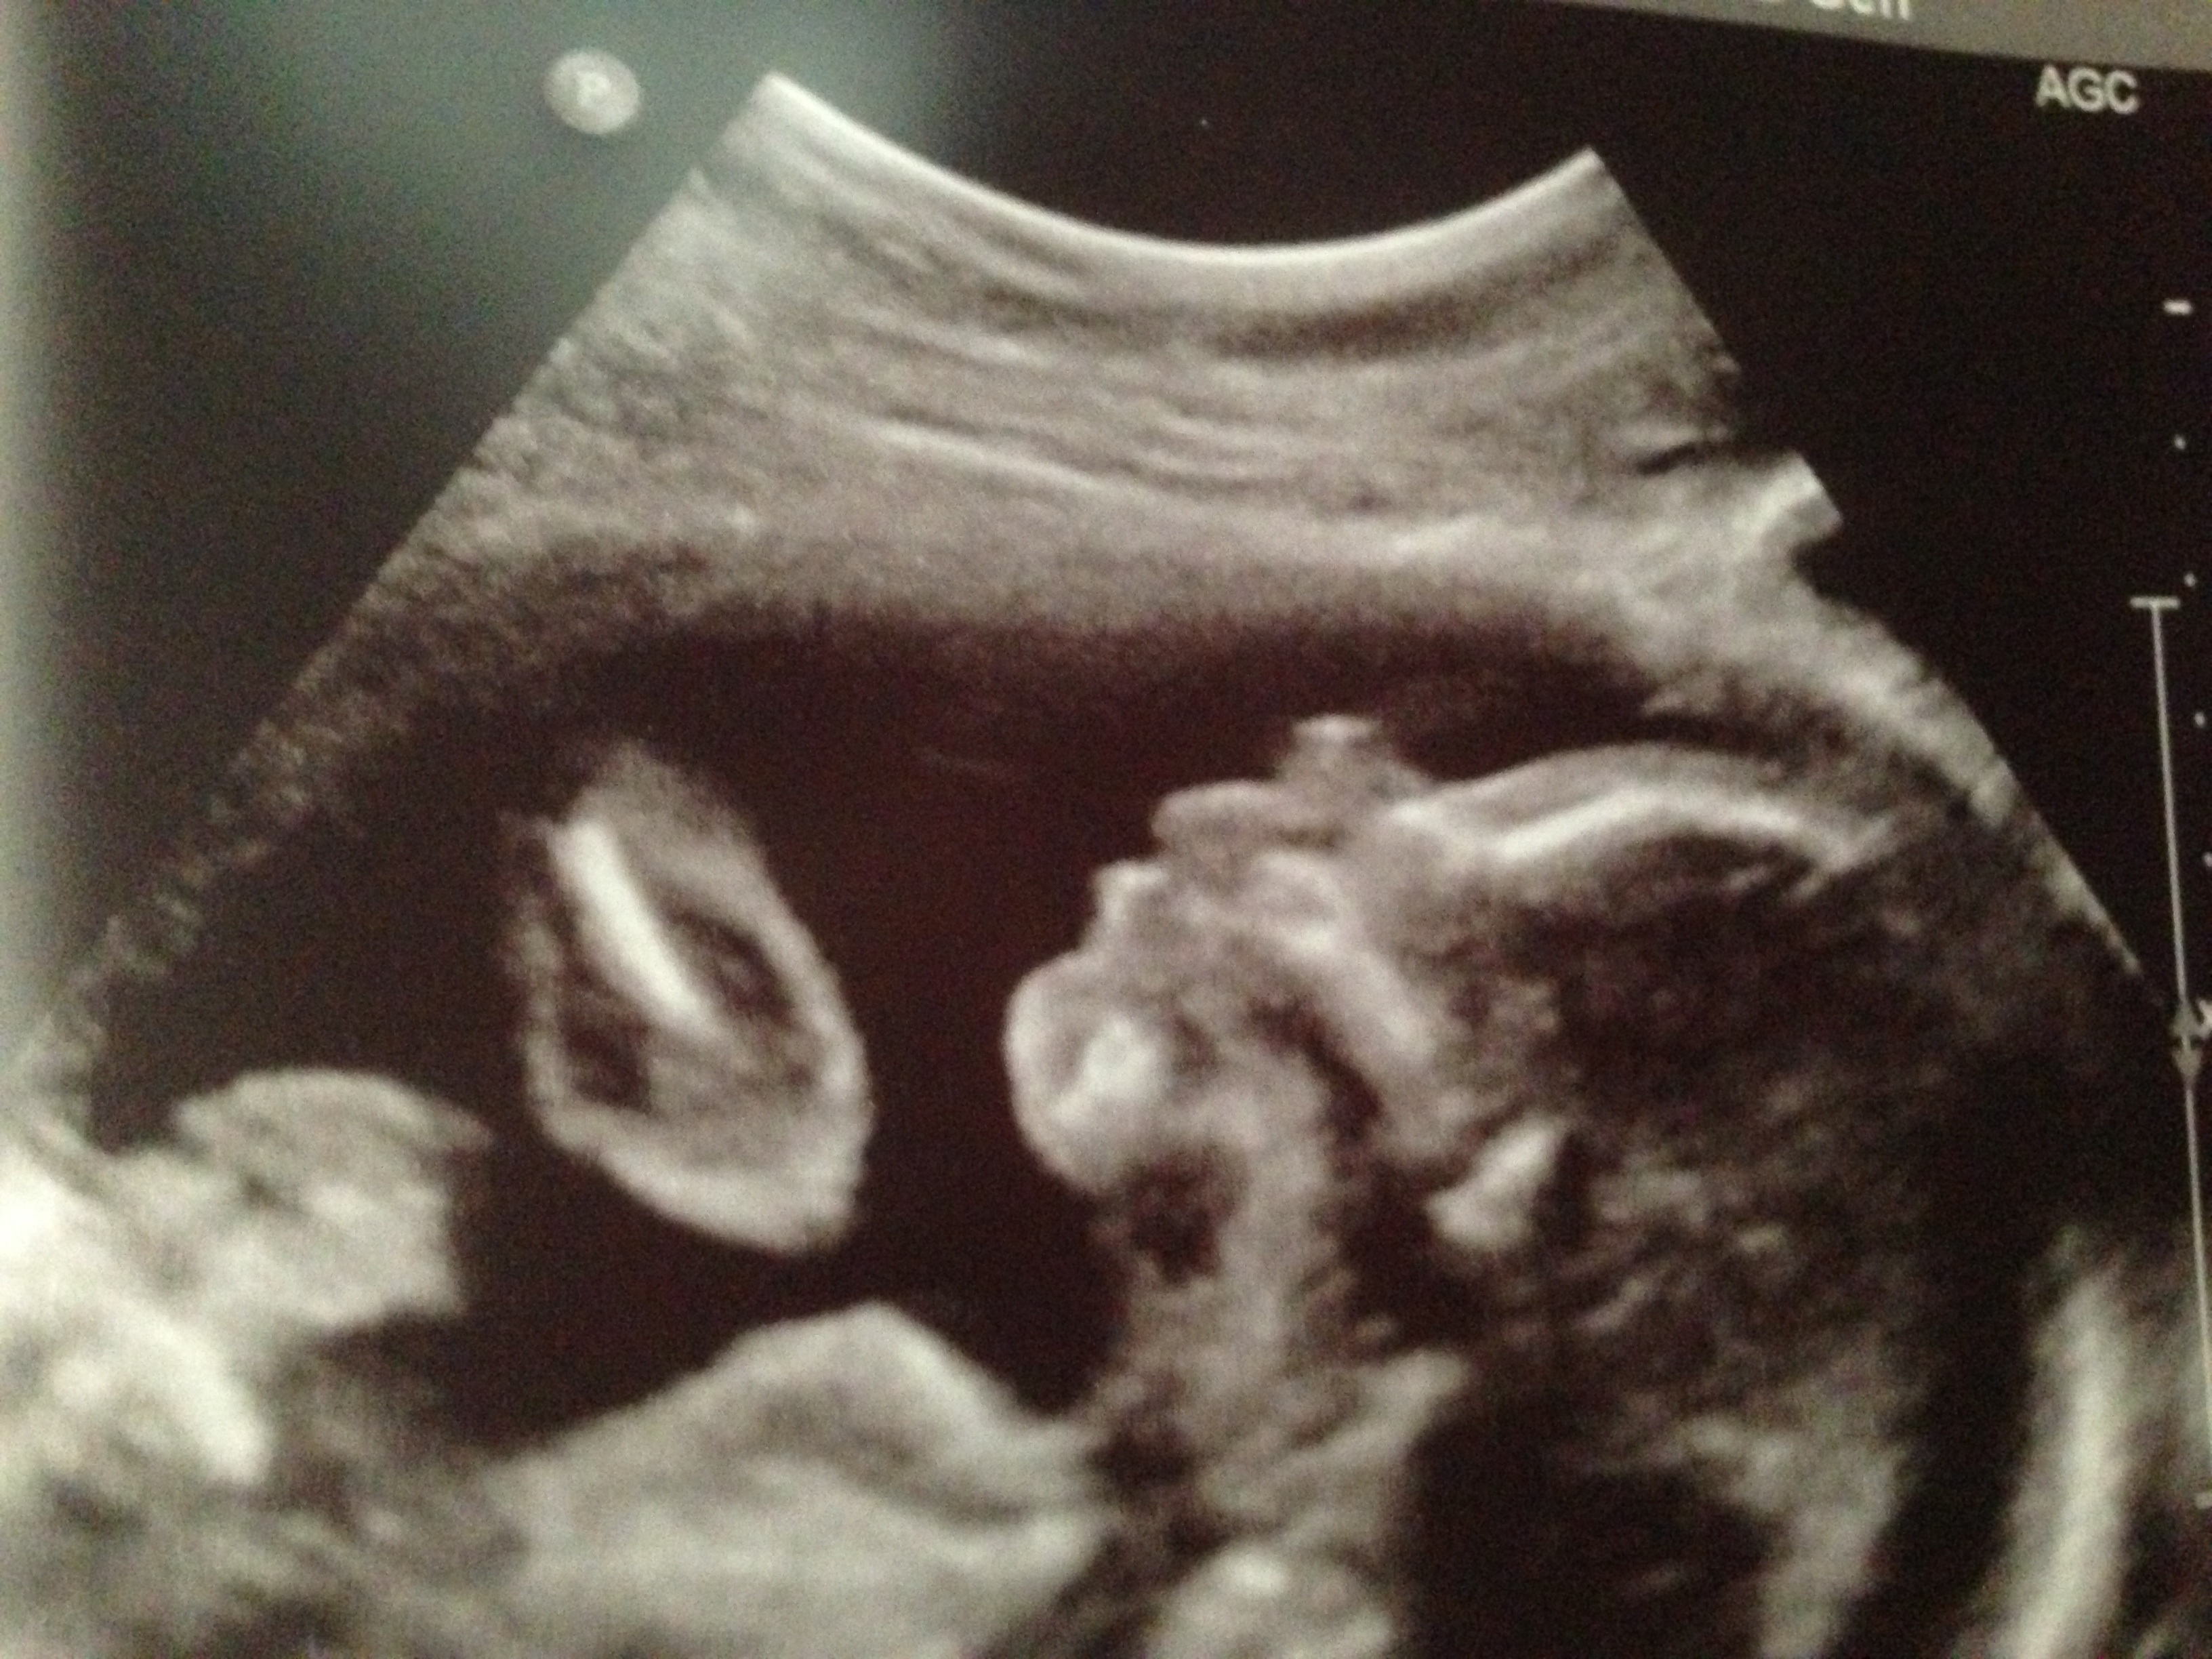

Photo from Sunday at 20 weeks. Profile of baby boy #3. I love that DH is able to feel this baby move more and more. Hoping within the next week or so, my boys will be able to feel it. He's getting really active in there!